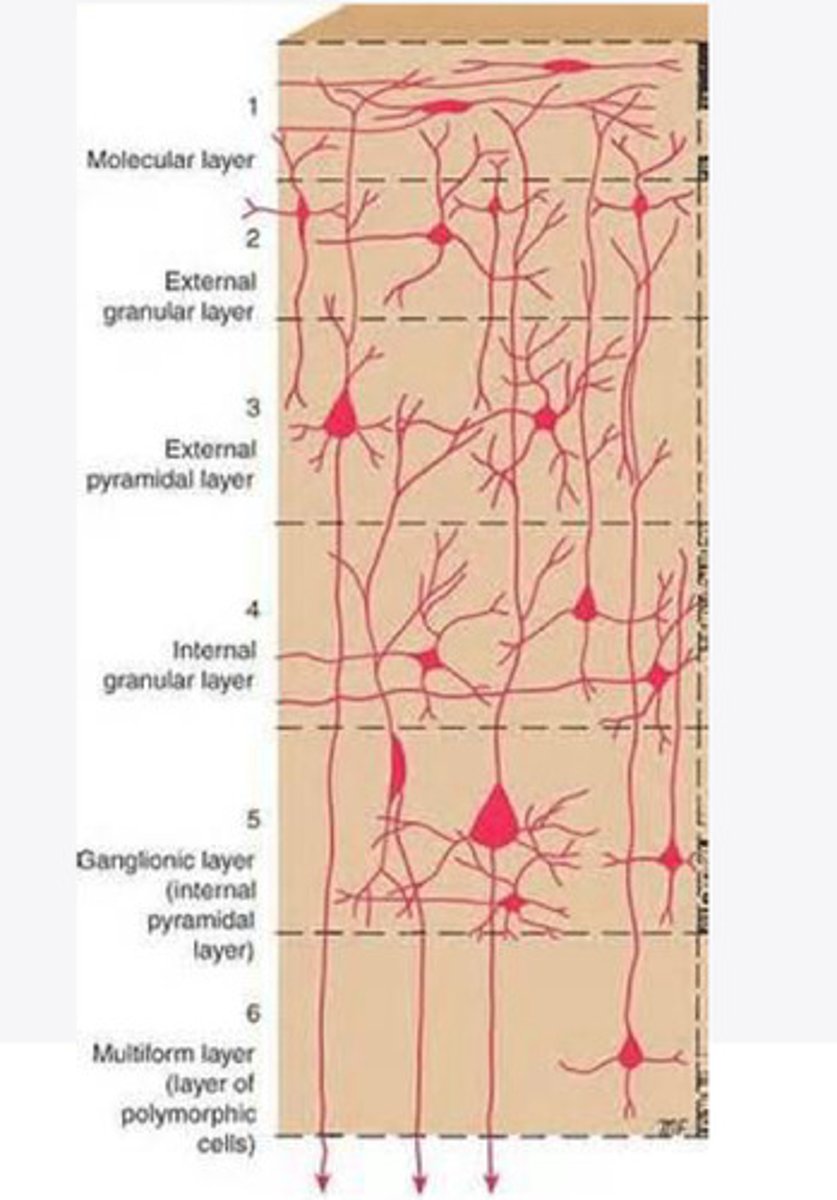

divided into 6 distinct layers, due to varying densities of cell body types within each layer

The cortex of the brain is divided into how many layers? Why is it divided into layers?

stellate, pyramidal

What are the 2 primary cell types in the cortex of the brain?

Layers of the cortex of the brain pic

stellate cells

These cells of the cortex RECEIVE impulses from other areas. There are numerous dendrites

in the regions of cortex associated with signal input

Where are stellate cells heavily concentrated in the cortex of the brain?

pyramidal cells

These cells of the cortex SEND impulses to other areas. Have 1 apical and 2 basal dendrites with a large axon

in regions of the cortex associated with sending output

Where are pyramidal cells heavily concentrated in the cortex of the brain?

2 and 4

What are the layers of the cortex that are associated with input?

3 and 5

What are the layers of the cortex that are associated with output?

molecular layer

What is the name of Layer 1 of the cortex of the brain?

very few cells

Does Layer 1 of the cortex have a lot or few cells?

receives dendrites from internal layers so it may actually function as a coordinating center where layers can communicate action

What does Layer 1 of the cortex do?

1

Every layer sends densities to Layer ____?

1

What layer serves as the "water cooler" of the brain?

external granular layer

What is the name for layer 2 of the cortex of the brain?

receives input from other cortical regions

What is the function of Layer 2 of the Cortex of the brain?

Stellate

What type of cells (stellate/pyramidal) would be most concentrated in Layer 2?

external pyramidal layer

What is the name for layer 3 of the cortex of the brain?

sends output to the other cortical layers

What is the function of Layer 3 of the cortex of the brain?

pyramidal

What type of cells (stellate/pyramidal) would be most concentrated in Layer 3 of the brain?

Layers 2 and 3

What layers are associated with association and commissural fibers?

Layer 3 - axons of cell bodies

Layer 2 - synapse into target areas in Layer 2

What part of the axons is in Layer 2/ in layer 3?

Layer 3 - external pyramidal layer

All axonal cel bodies for association and commissural fibers lie within what layer of the Cortex of the brain?

internal granular

** or called the striate cortex because it is so thick that you can see a line through this layer even in unstrained brain slides

What is the name for the 4th layer of the cortex of the brain?

receives input from the thalamus, geniculocortical layer, and other brainstem areas

What is the function for the 4th layer of the Cortex of the brain?

very thick within the vision, auditory, and somatosensory areas

Is Layer 4 thick or thin within SENSORY areas of the cortex?

Internal pyramidal

What is the name for Layer 5 of the cortex of the brain?

sends axons to the brainstem (corticobulbar) and spinal cord (corticospinal)

What is the function of Layer 5 of the cortex of the brain?

in motor areas of the cortex?

Where is layer 5 very thick in the brain?

the frontal lobe -- very motor heavy

What lobe of the brain will have a thick layer 5 of the cortex of the brain?

the multiform layer

What is the name of layer 6 of the cortex of the brain?

-sends axons back to the thalamus through corticogeniculate fibers

-modulates what information the thalamus sends to the cortex to control the strength of the signal received and modulate what you pay attention to

What is the function of layer 6 of the cortex of the brain?

no

Is layer 6 a motor layer?

without knowledge?

What are a priori decisions?

Yes, Layer 6 allows the cortex to make these decisions with corticogeniculate fibers

Can Layer 6 of the cortex of the brain make a priori decisions?

Symptoms experienced by TBI

Damage to Layer 6 of the cortex of the brain can play a role in what symptoms?